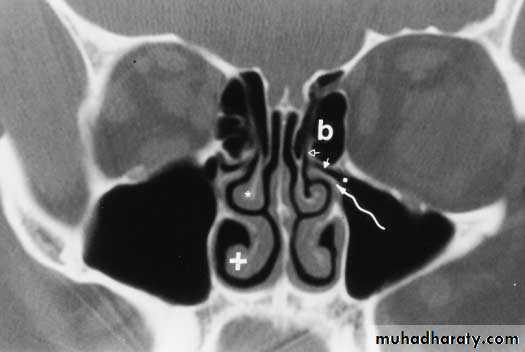

Lateral wall